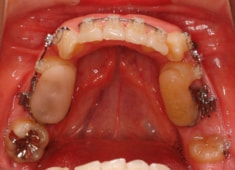

治療後(3年2ヶ月後)